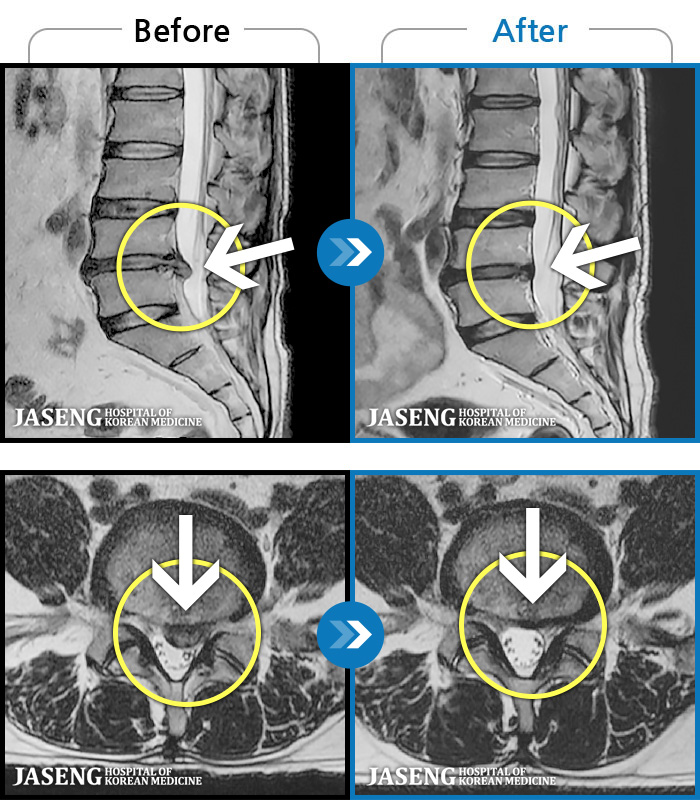

ȯںп Ǹ ǿ ԿǾ, ο ġ ۿ Ƿ ġḦ Ͻñ ٶϴ.